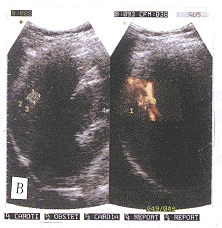

肝血管瘤是因为肝内小血管组织感染,肝组织局部坏死或肝内出血,血肿机化等原因造成肝内局部血循环停滞,血管海绵状扩张,静脉淤血膨大形成血管瘤。或因为肝内小血管发育异常,形成蜂窝状大小不一血窦,血窦间为纤维间隔,间杂血管和胆管〔1〕。因此病灶内血流极为缓慢或相对静止。CDFI对血流的显示是依据血流速度和角度的密切关系,低速血流及角度大于60°则CDFI敏感性降低。CDFI对肝血管瘤中的极低血流或相对静止的血流是不敏感的,本组中CDFI能显示的血流可能是来自于病灶外较粗静脉血管的分支(图1)。本组CDFI对病灶内血流显示率仅为22.47%。PDI是以能量方法显示血管内血流,仅与血管内红细胞等散射体数量有关,以能量信号作为成像参数,与单位面积内红细胞通过的数量及血流中红细胞的密度有关〔2〕,不依赖于声束与血管成角大小及检查时探头放置的角度。只要病灶中有极低速血流或红细胞产生运动都可以被PDI显示。PDI敏感性是CDFI的3~5倍〔3〕。本组中PDI能很敏感地显示部分病灶内低速血流。部分病灶内血流相对静止,但随呼吸运动,血窦内红细胞而产生运动,产生极低速血流;或因呼吸气屏气,腹腔压力增高,肝静脉血管内压力增高使血管瘤内血窦扩张,血窦内红细胞产生运动,这种细胞运动难以产生频移差,所以CDFI对之不敏感,而PDI则能敏感地显示,以充满型血流图表现即“繁星闪烁”征(图2)。部分病灶以点状、杆状或条状显示能量血流图。本组PDI对病灶内血流显示率高达96.6%。因而PDI对肝血管瘤的诊断较CDFI有很高的应用价值。

A图为CDFI显示较粗血流图为肝右静脉分支,血流分级Ⅰ级。

B图为PDI能直观显示血管瘤与肝右静脉关系,血流分级Ⅳ级。

图1 血管瘤位于肝右静脉右侧,大小9mm×8mm